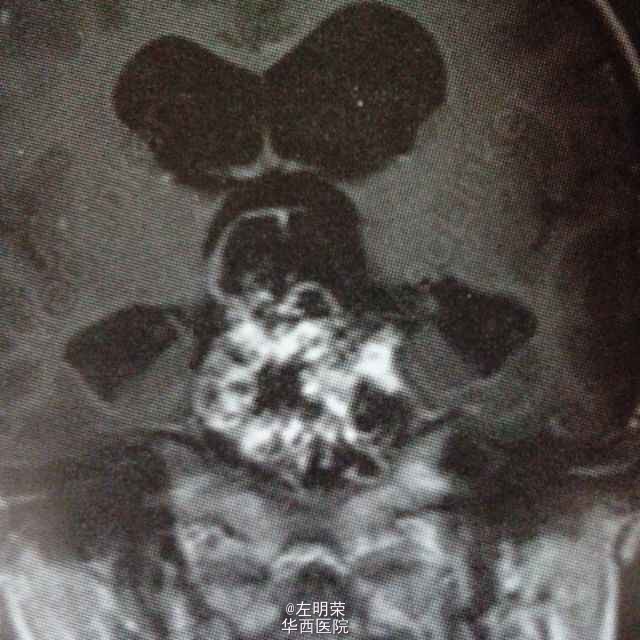

女,6岁,以间断头痛3个月余,加重2个月之主诉入院。MRI示:桥前池-鞍上池-三脑室内巨大不规则均匀强化影,鞍背骨质可见破坏,病灶内可见囊变坏死区。可见脑干及病灶周围实质明显受压移位,病灶与脑实质分界清楚;考虑诊断脊索瘤,颅咽管瘤,神经鞘瘤。术中见肿瘤囊实性,血供丰富,边界尚清,位于鞍背上方,脑干前方,与基底动脉,大脑后动脉粘连紧密,给予全部切除;病理示:神经鞘瘤。